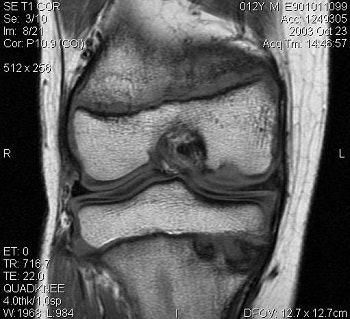

![]() |

| JOCD of the capitellum. Coronal T2-weighted image (A, above), sagittal T1-weighted image (B, middle) and coronal T1-weighted image with fat saturation (C, below) demonstrate disruption of the articular cartilage (black arrows in images figures A and C) and the crescentic subchondral signal abnormality (white arrows in figures A and C) that is typical of an osteochondritis dissecans lesion. Images courtesy of Dr. Douglas Beall. |